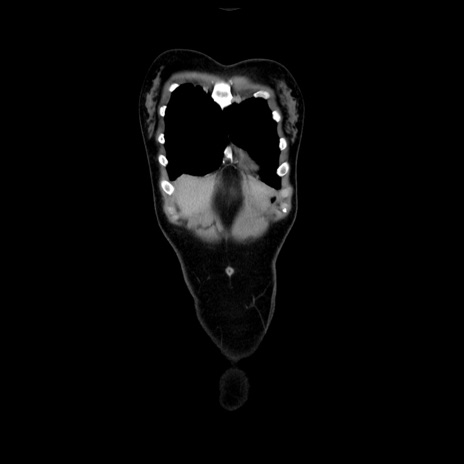

症例39(冠状断像)

【症例】40歳代女性

【主訴】上下腹部痛

【現病歴】2日目から下腹部痛あり。夜間は痛みで眠れなかった。昨日より上腹部痛と下痢が出現。臥位で痛みは軽快したため、休んでいた。本日になって臥位でも立位でも痛みが強くなってきたため救急要請。

【既往歴】子宮内膜症

【身体所見】部:平坦・軟、左上下腹部に圧痛あり、反跳痛あり。

【データ】WBC 21800、CRP 26.78

CT